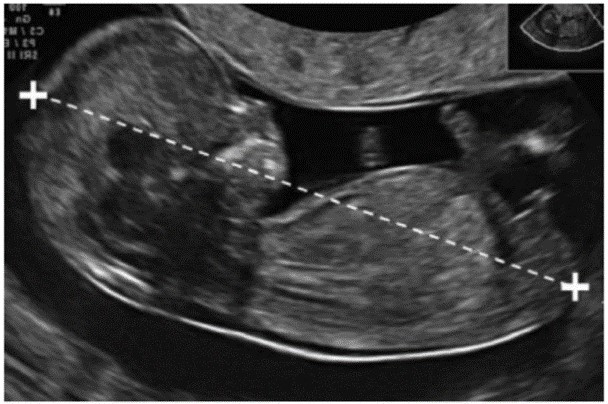

![]() |

| Figure 2. The length of the rump (A) and the light at the back of the neck (B) |

(A) (B)